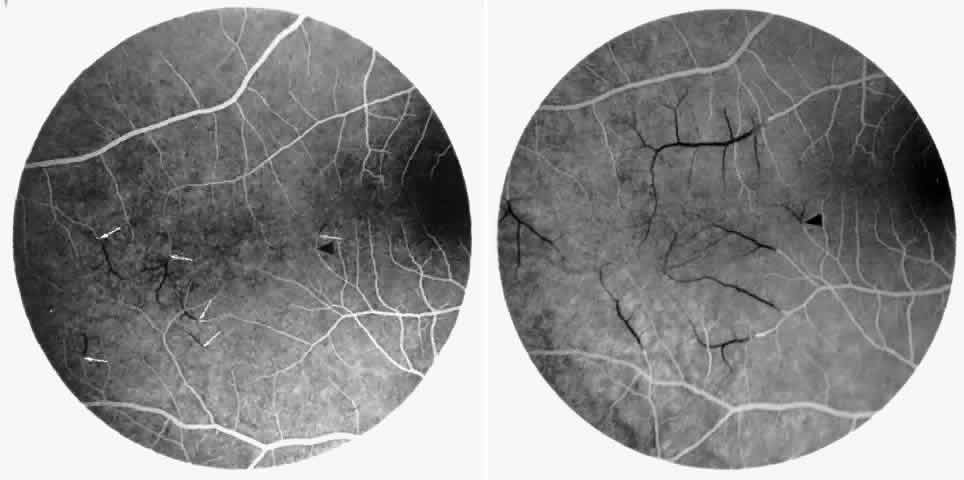

STAGE II: PERIPHERAL ARTERIOLAR-VENULAR ANASTOMOSES. Following occlusion of the terminal arterioles, anastomotic channels form to channel the blood from the occluded arteriole to the nearest venules. These anastomoses form at the interface between the perfused and nonperfused retina. Most likely, they are dilated preexisting capillaries rather than new vessels, since they do not leak on fluorescein angiography. The redirection of blood flow is probably due to hydrostatic forces (Figs. 22 and 23).

Fig. 22. A. Photograph of the peripheral retina, demonstrating capillary occlusions and exudate at the margin of perfused retina. B. Fluorescein angiogram of irregular capillary border, with capillary stumps extending into nonperfused retina and an arteriolar-venular anastomosis demonstrating stage II retinopathy.

Fig. 23. Fluorescein angiogram of continuous arteriolar-venular anastomosis demonstrating stage II retinopathy. (Note that this is the same eye demonstrating the qualitatively abnormal peripheral capillary border in Figure 25.)